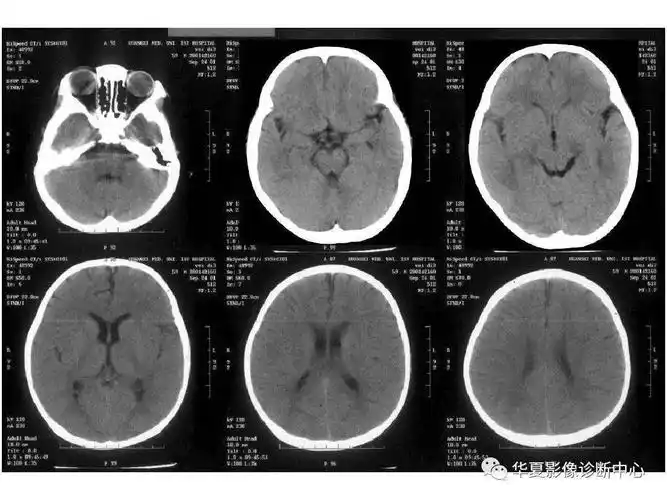

67超急性期大面积脑梗死ct平扫表现

患者入院后头颅ct提示蛛网膜下腔出血,以脑干前方为主,提示后循环

头部ct影像解剖

颅脑ct怎么看正常和异常影像分别是什么